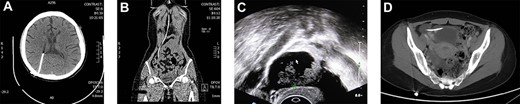

A 25-year-old unmarried female came to our hospital with a complaint of gradual enlarging mass in right adnexa about 1 year without pain. The patient had medical history of receiving VPS 16 years ago due to hydrocephalus (Fig. 1a and b). Laboratory results were as follows: cytosine arabinoside (CA) 19–9: 49.34 U/ml (0–35) and CA 724: 19.6 U/ml (0–6.9). Hematopoiesis and clotting activity, as well as functions of the liver and kidneys were all normal. The results of ultrasound of gynecology and pelvic CT scan are shown (Fig. 1c and d). Abdominal ultrasound indicated multiple angiomas were observed in the liver and spleen.

(A and B) CT showed the shunt from lateral ventricle to abdominal cavity; (C) Ultrasound of gynecology showed a mass measuring about 3.5 × 2.3 cm in the right adnexa, which was mainly cystic, with solid irregular protrusions ranging from 2.7 × 1.6 cm inside, in which blood flow signals were explored; (D) Pelvic CT scan suggested drainage catheter was located in the front of the uterus.